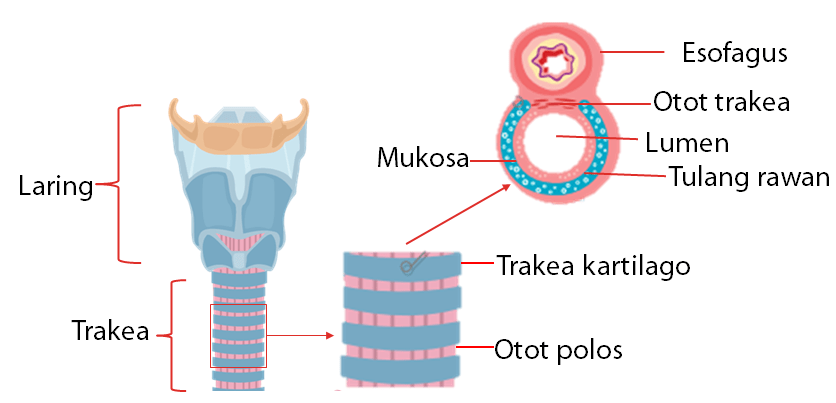

3. Laring

Di dalam laring terdapat sebuah katup yang disebut epiglotis. Epiglotis berfungsi mengatur jalannya makanan dan udara pernapasan sesuai dengan salurannya masing-masing. Di samping itu, pada pangkal tenggorokan terpadat pita suara yang merupakan organ penghasil suara pada manusia. walaupun demikian, saraf kita akan mengatur agar peristiwa menelan, bernapas, dan berbicara tidak terjadi bersamaan sehingga mengakibatkan gangguan kesehatan.

4. Trakea

Tenggorokan berupa pipa yang panjangnya ± 10 cm, sebagian terletak di leher dan sebagian terletak di rongga dada. Dinding tenggorokan tipis dan kaku, dikelilingi oleh cincin tulang rawan. Pada bagian dalam rongga terdapat epitel bersilia. Silia-silia ini berfungsi menyaring benda-benda asing yang masuk ke saluran pernapasan.